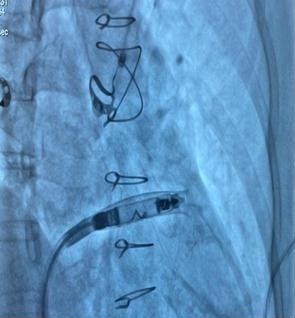

Under fluoroscopic guidance, the delivery catheter was advanced through the right atrium. Significant resistance was encountered as the catheter tip repeatedly abutted the ventricular wall due to the limited chamber size. To overcome this, the catheter was reshaped into a “hockey-stick” configuration developed by our team (Fig. 4–9). This modification enabled safe passage through the tricuspid valve and facilitated navigation to the apical-septal region. Contact mapping confirmed optimal electrical parameters before fixation, and the device was screwed into the septum. Device interrogation demonstrated proper function: pacing threshold 0.75 V at 0.4 ms, R- wave amplitude 6.0 mV, impedance 750 Ω, mode VVI, with estimated battery longevity of ~12 years.

Figure 4. Modified 'hockey-stick' curvature of the delivery catheter guiding the pacemaker toward the right ventricle

At the junction of the superior vena cava and right atrium, maximal deflection of the distal catheter segment was applied, followed by slight retraction, creating an acute 70–90° bend resembling a “hockey stick.” This configuration shortened the working length, allowing maneuverability in the restricted RV cavity. Crossing the tricuspid valve was guided by RAO 30° and LAO 40° projections to ensure septal alignment. In the apical-septal region, contact mapping (with the helix unreleased) confirmed acceptable parameters (R-wave ≥5 mV, threshold ≤1.0 V at 0.4 ms, impedance 400– 1500 Ω). Upon satisfactory values, the device was screwed into the septum with 1.5 turns. Perpendicular positioning was confirmed in orthogonal views, followed by a tug test. Repositioning was feasible if parameters were suboptimal.